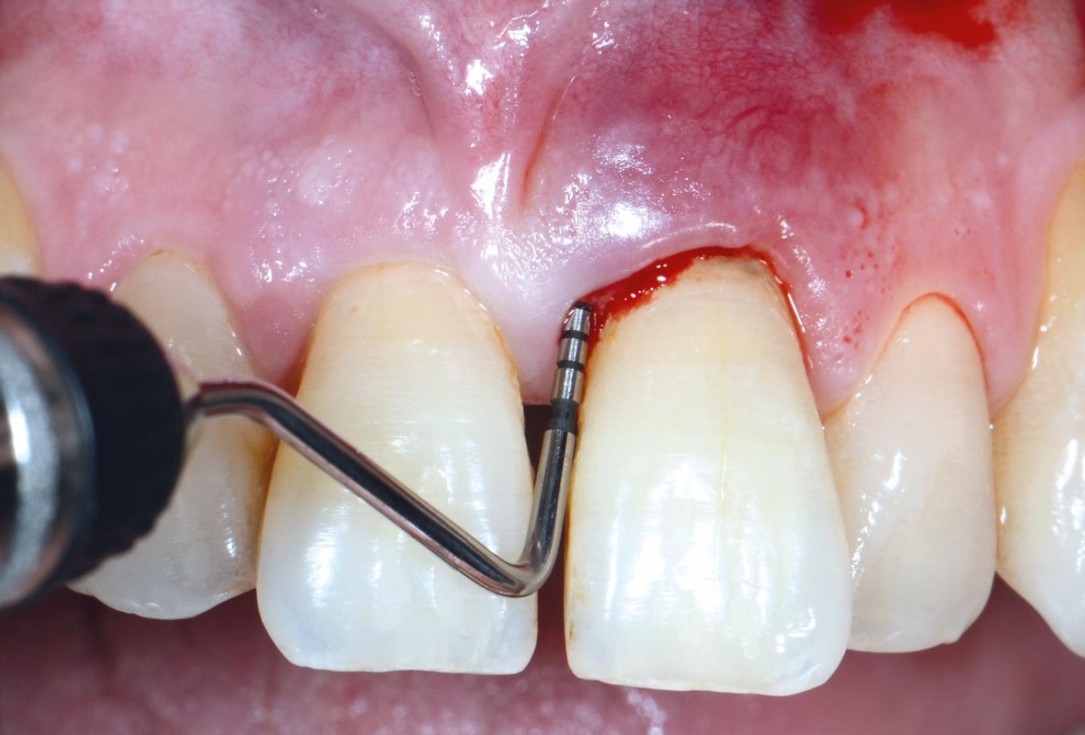

02/11 - Initial probing depth of 12 mm before non-surgical therapyEntire papilla preservation technique (EPP) for the regenerative treatment of a severely compromised central incisor - Dr. S. Aslan